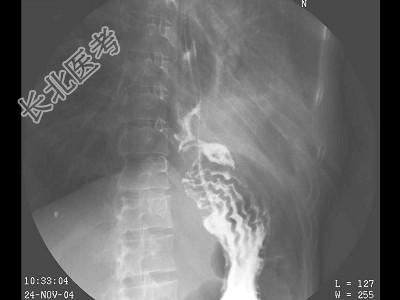

- 单项选择题女,39岁, 左下肺叶切除术后。体检:左下肺呼吸音弱, 行胸腔闭式引流术,引流出脓性分泌物。结合图像, 最可能的诊断为 ( )

E、食管下段胸腔瘘